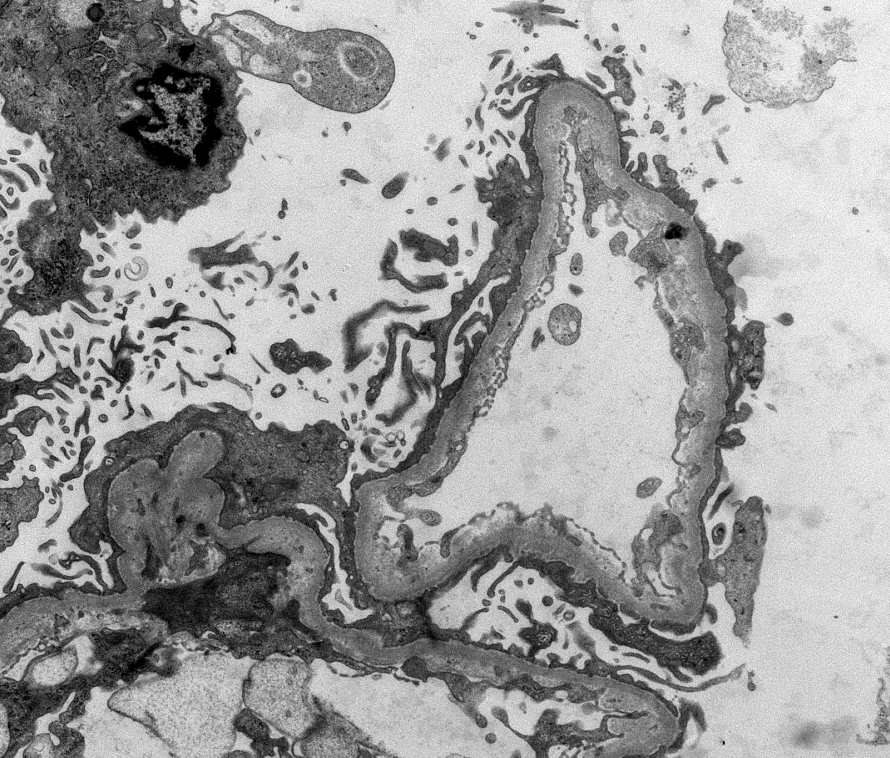

BK nephropathy Clues: - Heavy but focal tubulointerstitial inflammation - Increased plasma cells - Viral cytopathic change - Features of CNI toxicity ->over immunosuppression (isometric vacuolization shown here) -SV40 IHC confirmatory #renalpath #pathtwitter #nephrology